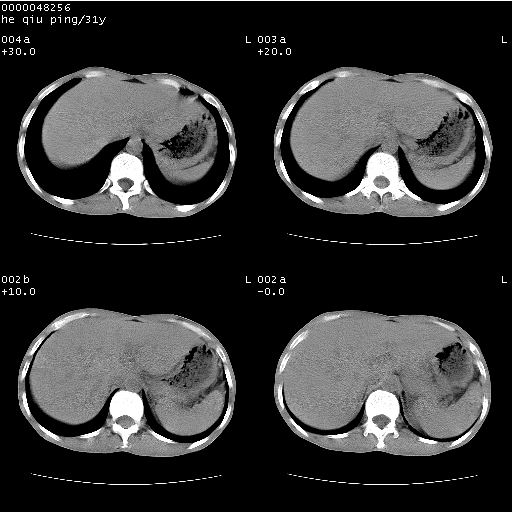

标题: CT13402:M,31Y。肺结核伴空洞形成? [打印本页]

标题: CT13402:M,31Y。肺结核伴空洞形成?

咳嗽半月余,消瘦体质,呼吸音弱。无其他病史。cr:肺转移瘤待。